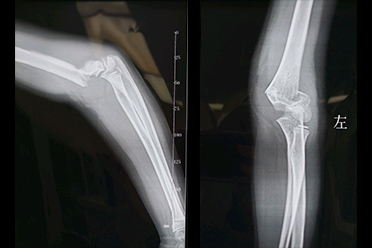

肱骨髁上骨折根据外伤*力暴**的不同和骨折移位的方向分为伸直型和屈曲型。伸直型肱骨髁上骨折儿童多有手部着地病史,肘部出现疼痛、肿胀、皮下瘀斑。肘部向后突起并处于半屈位。肘部x线显示骨折近端向前下移位,远骨折端向上移位。

面对这种骨折时,我们不仅要想到骨折,还要想到血管和神经的损害。屈曲型肱骨髁上骨折多是孩子跌倒时,肘关节屈曲位时着地引起的骨折。受伤后,局部出现疼痛,肿胀,肘后瘀斑。肘部x线显示骨折近端向后下移位,远端向前移位,骨折线呈现前上斜向后下。